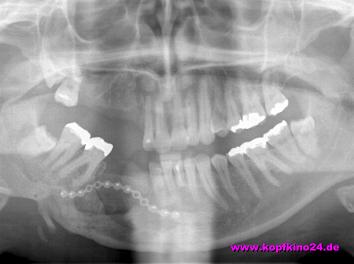

Anfang Mai 2004 begann der Knochenaufbau im Unterkiefer. Zur Erinnerung: dort fehlte mir ein 2 x 2 cm großes Stück Kiefer. Dafür wurde ein Stück Knochen (Blockimplantat) aus dem Beckenkamm entnommen.

Dieses Stück Knochen wird mit einer neuen Platte in Position gehalten und wächst dort hoffentlich fest ein.

Als nächstes war im August 2004 die Zahnimplantierung im Unterkiefer geplant. Es werden dabei zwei "Metallhülsen" in den Kiefer eingebracht. In diese Hülsen werden nach weiteren 6 Monaten der Einheilung die neuen Zähne verankert.

Der Unterkiefer wurde vom Metall befreit, welches das Stück Beckenkamm fixierte. Das ist gut eingeheilt. Und so wurden dort 2 Implantate für die weitere prothetische Versorgung gesetzt. Die müssen jetzt wiederum ca. 4 Monate einheilen, bevor es dort weiter gehen kann.

Der nächste OP-Termin steht bereits schon an: am 22.11.04 gehts es wieder ins Krankenhaus. Dann wird im Oberkiefer Knochen aus dem Becken eingebracht und somit mein Oberkiefer rekonstruktruiert.

Jetzt wird im Oberkiefer "weitergewerkelt".

Die dort fehlenden 4 Zähne laß ich mir auch über Implantate ersetzen. In meinen jungen Jahren will ich mich nicht mit einer Prothese rumärgern müssen.

Die Übergangsprothese ist für den Übergang ganz o.k. - aber nicht ein Leben lang.

Bevor allerdings implantiert werden kann, muß auch hier der Kiefer wieder aufgebaut werden: da fehlt in Höhe und Breite Knochenmaterial. Dabei kommt wieder körpereigenes Material aus dem Beckenkamm zum Einsatz.

Bestimmte, sehr kleine Knochendefekte können auch mit einer künstlichen Knochenmasse aufgefüllt werden. Diesem Granulat werden eigene Knochenkrümmel beigefügt. Somit wird dem Körper "eigenes" Material vorgegaukelt und es heilt dann problemloser ein

Aufgrund meines beträchtlichen Kieferknochenverlustes ist diese Variante aber nicht machbar.

Bei der OP wurde ein Sinuslift sowie ein Aufbau des Kieferknochens vorgenommen. Beim Sinuslift wird die Kieferhöhlenschleimhaut angehoben, um Platz für das einzusetzende Knochenstück zu schaffen. Durch den Unfall fehlte es mir an Knochenhöhe im Inneren - von außen gar nicht so extrem wahrnehmbar. Die späteren Implantate brauchen aber eine entsprechende Knochenhöhe für einen stabilen Halt.

Von außen sichtbarer war vielmehr, dass mein Kiefer schmaler als normal war. Um dies auszugleichen - und den Implantaten Halt zu geben - wurde der Kiefer auch "verbreitert". Dazu spaltete man den vorhandenen Kiefer der Länge nach und in diesen Spalt wurde ein Stück aus dem Beckenkamm eingebracht. Zur Fixierung drehte man zwei Schrauben durch den neu geschaffenen Oberkiefer. Der muß jetzt erst mal wieder ca. 3-4 Monate einheilen. Dann kann dort implantiert werden.

Wenn die Zähne prothetisch wieder hergestellt sind, heißt es für mich eine Zahnspange tragen, da meine oberen Schneidezähne durch den Unfall nicht mehr an Ort und Stelle stehen.